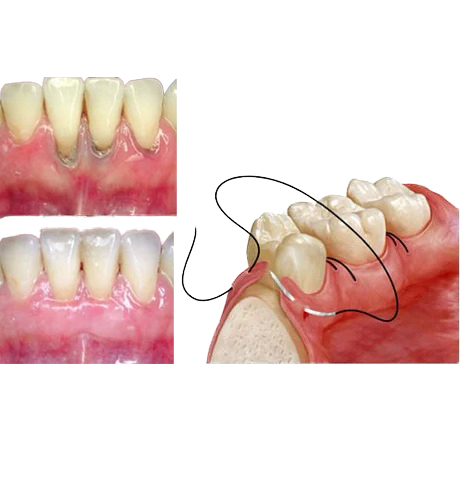

TEETH GUM TREATMENT

Welcome to Vyshnavi Dental Hospital, your destination for top-notch Teeth & Gum Treatment. Our expert team of experienced dentists is dedicated to providing comprehensive care, from preventive measures to advanced procedures. Whether it's routine check-ups, teeth cleaning, gum disease management, or specialized treatments like dental implants, we prioritize your comfort and well-being. With state-of-the-art technology and a patient-centric approach, we ensure you leave with a confident smile. Trust us for personalized care and exceptional results. Your dental health is our priority!